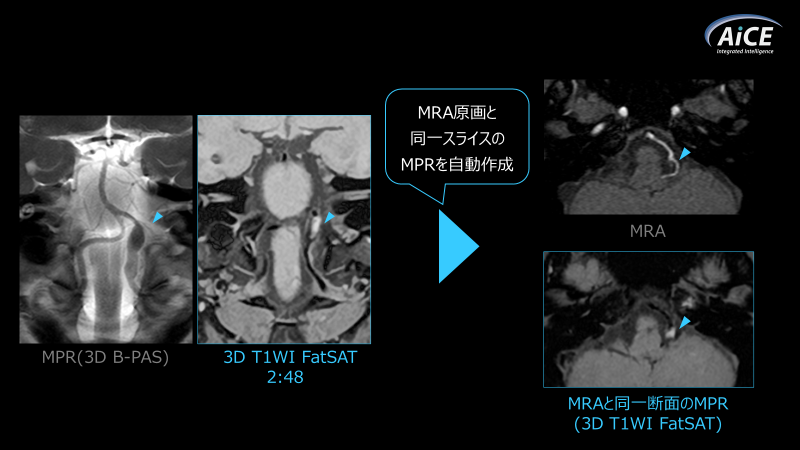

当院では時間短縮のため、ガントリ上のStartボタンを押して操作卓に向かうワークフローでしたが、新機能の「AutoStart」により、ドアを閉めると自動的に検査開始できるようになりました。また、位置決めアシスト機能「NeuroLine+」を常に使用しており、自動的に断面を合わせてくれます。さらに、認識した断面は断面連動機能「オートリンク」にて各シーケンスへ適応され、ルーチン検査ではコンソールをほとんど触らずに検査を進めることができます。空き時間に後処理ができるため、理想的なワークフローを実現しています。また、同グループに整形外科クリニックも併設しており、整形領域ではMPR画像を用いて事前に撮像断面を確認できる「ForeSee View」を活用することで、再撮像のリスクを軽減できています。加えて、画像再構成速度も向上し、MRAなどの3D撮像では明らかに速度が向上し、撮像後すぐに画像を確認できるようになりました。(Fig.6)後処理では、MPR処理に他の画像の位置・角度を参照して同一断面に再構成する機能が追加されました。この機能は撮像断面が異なる場合でも使用可能であり、例えば冠状断で追加撮像した椎骨動脈解離のBlack Blood画像を、軸位断の頭部MRAと同一位置でMPR再構成することが容易に行えます。これら機能により、画像比較や読影効率が向上し、時間短縮にも貢献しています。(Fig.7)